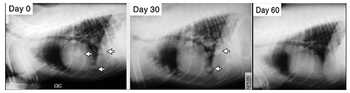

Diagnosing transitional cell carcinoma can be a difficult clinical challenge. Clinical signs (pollakiuria, dysuria, stranguria, and hematuria) are nonspecific, and differential diagnoses include granulomatous cystitis, other neoplastic diseases (lymphoma, rhabdomyosarcoma), a persistent or recurrent urinary tract infection, and urinary calculi-the latter two of which may occur concurrently with transitional cell carcinoma.